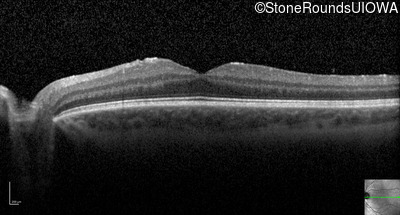

Optical Coherence Tomography - Right - 20/20

Exemplar / OCT Stack

Optical Coherence Tomography - Left - 20/20 -2